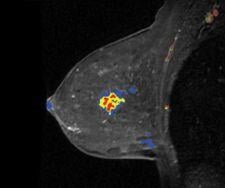

Confirma’s next-generation product for breast MRI includes a new customizable BI-RADS-centric user interface that accommodates a variety of user experience levels. Additional CADstream enhancements include improved 3D renderings and tools for morphology reporting.

The next generation of CADstream for breast MRI enhancements will include a customizable BI-RADS-centric user interface and improved volume summaries and morphology reporting tools. Additionally, the Company will debut the Access Breast Coil with high quality diagnostic capability, flexible interventional access and optimized patient comfort.